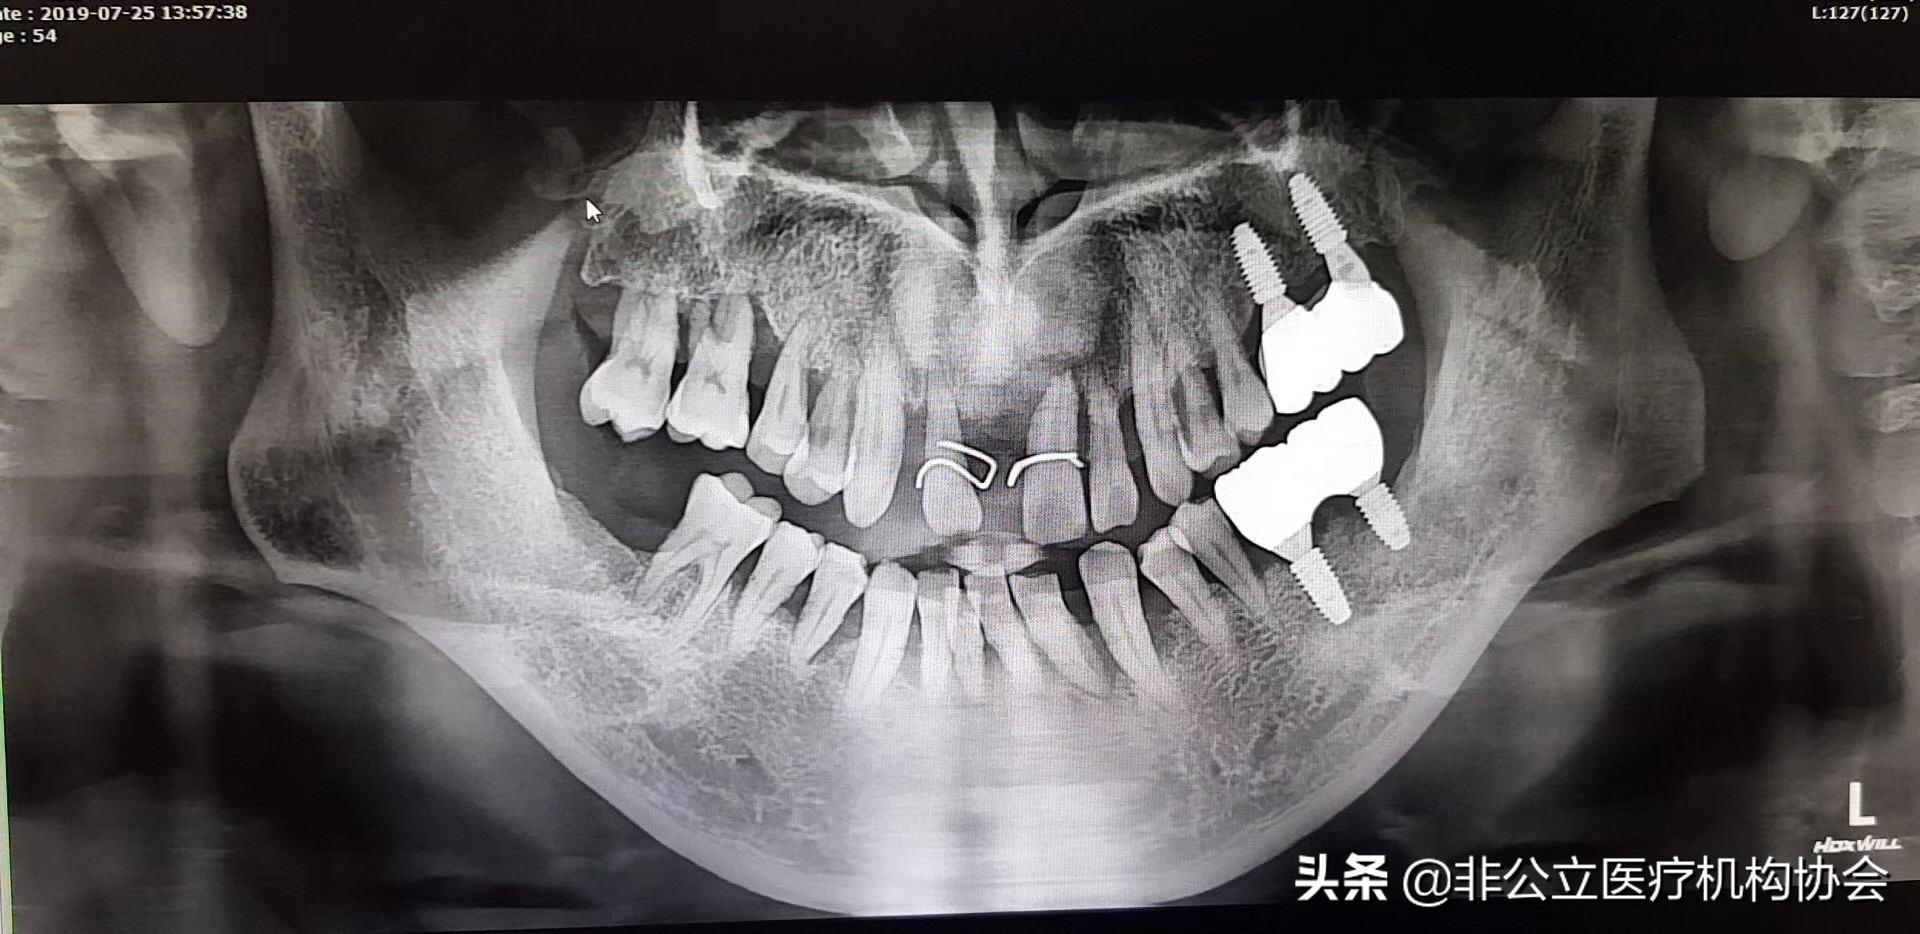

【此病例分為兩部分,這是第一部分】術(shù)前的X光片,54歲男,種四顆了,上下前牙。上下前牙牙周病了((一)

檢查:上下1、23度松動,排列不齊,牙石2度?,牙齦紅腫,輕探出血,CT 檢查水平吸收達根長1/3左右。有牙槽骨吸收。嚴重牙周病。